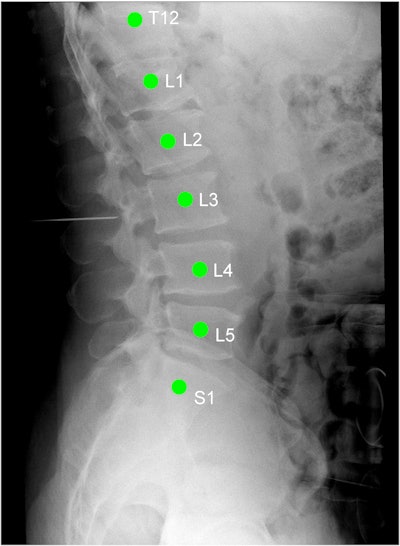

The LevelCheck algorithm is designed to automatically localize target vertebrae by registering preoperative 3D CT scans to 2D mobile x-ray images acquired in the operating room (OR). To localize spine levels, the process requires only that the target vertebra be labeled in the preoperative image -- for example, by pointing and clicking on a single vertebral area of interest. Then the same labels, in either their official anatomical names, such as T5 or T6, or in user-specific names such as "target," are placed on the corresponding spot on the radiograph.

In the current study, the researchers wanted to investigate LevelCheck's performance under real-world conditions. They used the algorithm to examine images from 20 consecutive patients undergoing thoracolumbar spine surgery; all had received preoperative CT and intraoperative mobile radiography scans, which were examined retrospectively.